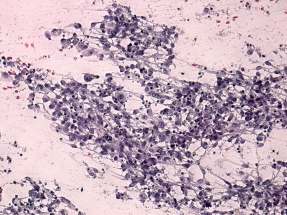

Cytological diagnosis: carcinoma - with great probability an adenocarcinoma in the lymph node. Benign colloid goiter in the thyroid.

Wash-out thyroglobulin of the lymph node resulted in 0 ng/mL.

On further evaluation an adenocarcinoma of the ascending colon was found and a right colectomy was performed.